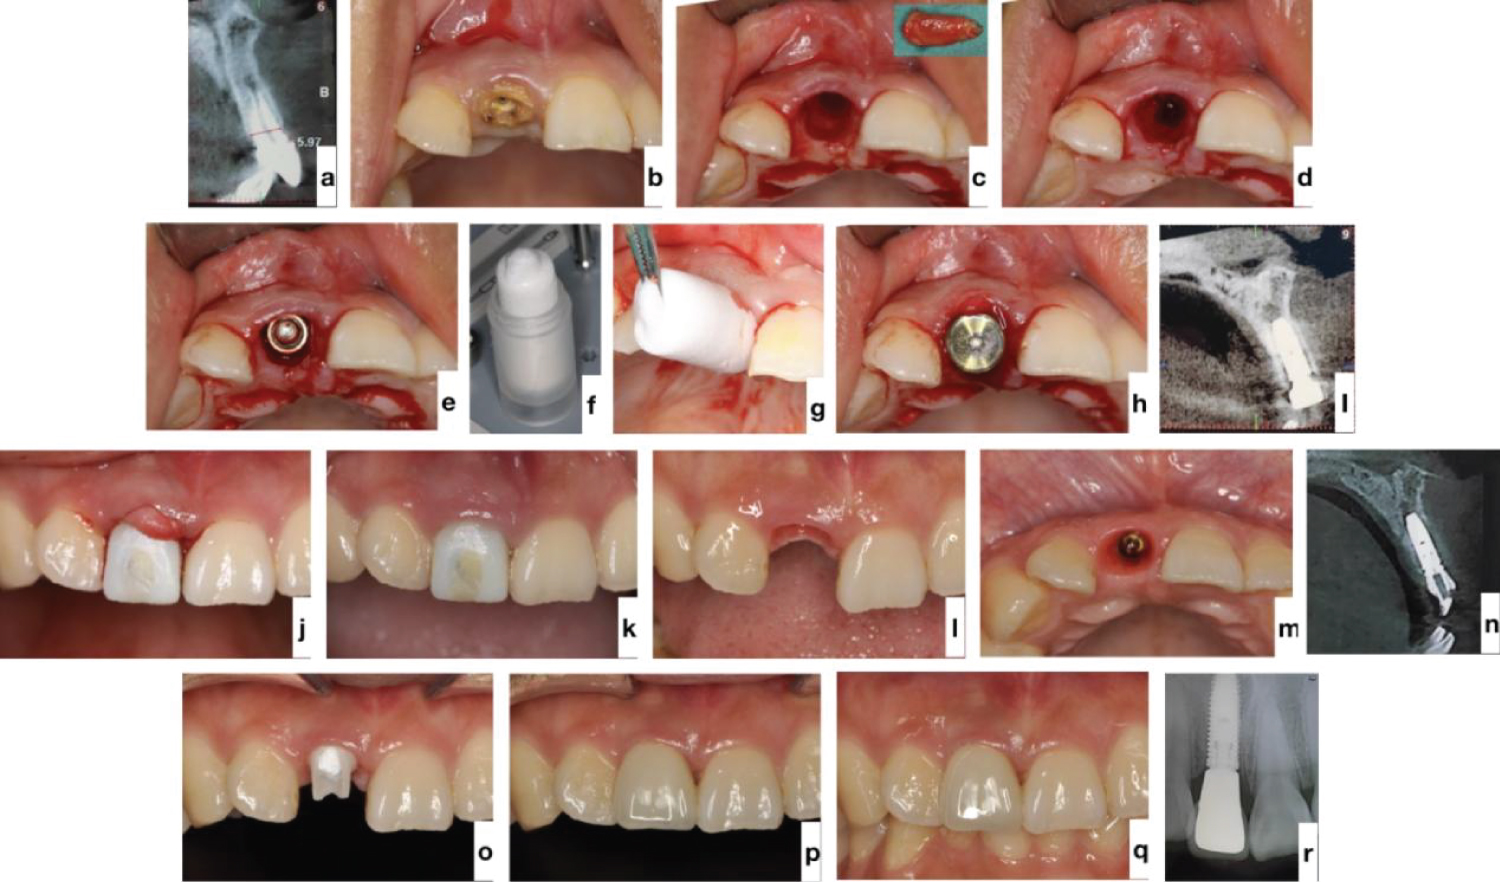

When an implant is placed into the fresh socket and a good primary stability is achieved, we should applied a healing abutment onto the implant. TERUPLUG ® should be folded into a “U” shape and stuffed into the gap at the buccal side and the interproximal side of the abutment subsequently, and vertically keep it out of contact with the threads of the implants if possible (Figure 3). Only in this way can clinicians exert TERUPLUG ® perfectly for soft- and hard-tissue augmentation.

Since 2018, our teams have attempted to apply TERUPLUG ® in immediate implant placement procedure, aiming at obtaining an excellent buccolingual volume that is coincident with the contour of the tooth either in the anterior region or in the posterior region.

In our experience, when the implant is placed to the palatal aspect of the fresh tooth extraction socket, a buccal residual gap distance of about 2 mm will be left there. Then, place a wide flat contoured healing abutment, and adapt a suitable size TERUPLUG ® into U-shape and insert it against the abutment into the gap at the facial and interproximal side, filling the bone and soft tissue zones, to reserve the space for peri-implant hard- and soft-tissue [45]. Make sure that the TERUPLUG ® occupies the soft tissue zone to the height of the free gingival margin (FGM) and keep it out of contact with the threads of the implants, only in this way can TERUPLUG ® act as a scaffold to support the ridge contour profile (Figure 3). At the anterior zone, immediate restoration can be considered, acting both as the prosthetic seal and as the biomaterial protection and supporter during initial healing.

When the secondary implant stability is obtained after 3-6 months healing period, the provisionalization is removed, and the matured soft tissue contour is presented, a provisional prosthesis copying the maintained emergence profile is placed and then the final contour is transferred with a custom impression transfer technique. Finally we can obtain a restoration simulating the natural tooth emergence, thus guaranteeing more predictable results and simplifying the next stages of treatment (Figure 5).